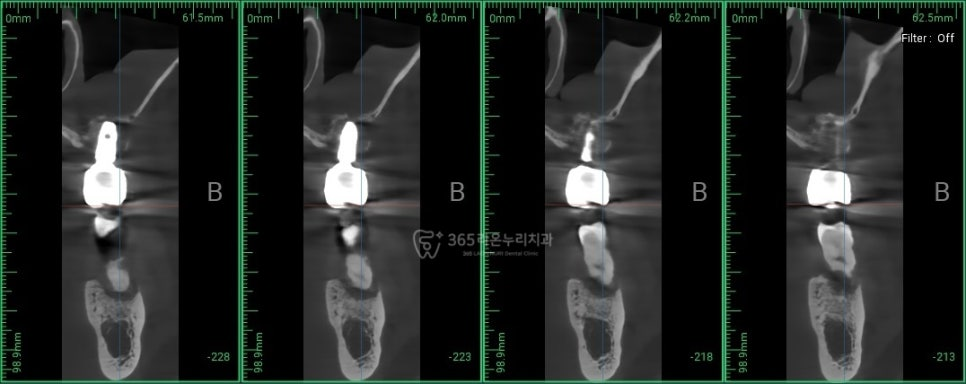

2025.01.10

먼저 시술 전 CT를 찍어 식립 각도와

방향 깊이등을 설정해줍니다.

보통 골 이식이 시행되며, 이후 식립하게 됩니다.